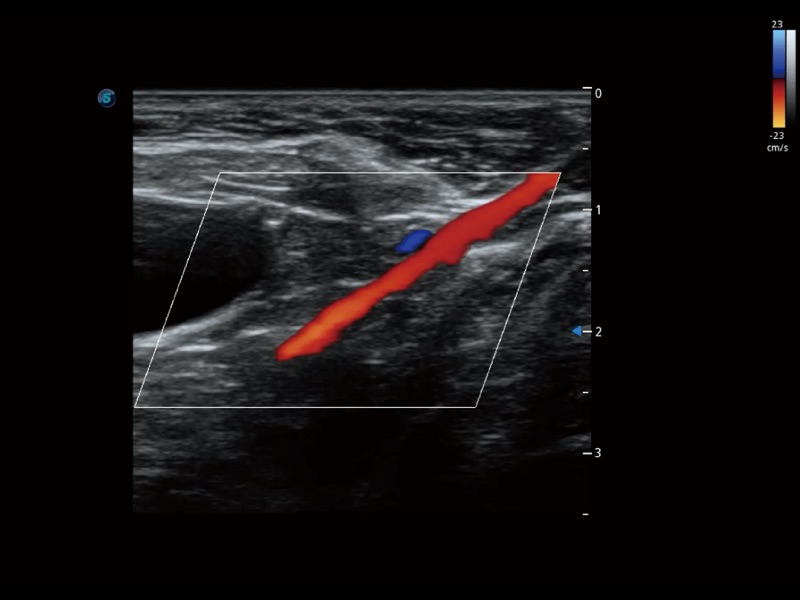

通過色彩血流和實(shí)時寬景相結(jié)合,可觀察到完整的靜脈或動脈的血流,方便醫(yī)生檢查。實(shí)時掃查過程中,如有任何操作失誤也可以很容易地進(jìn)行回掃擦除,而不會中斷掃查。